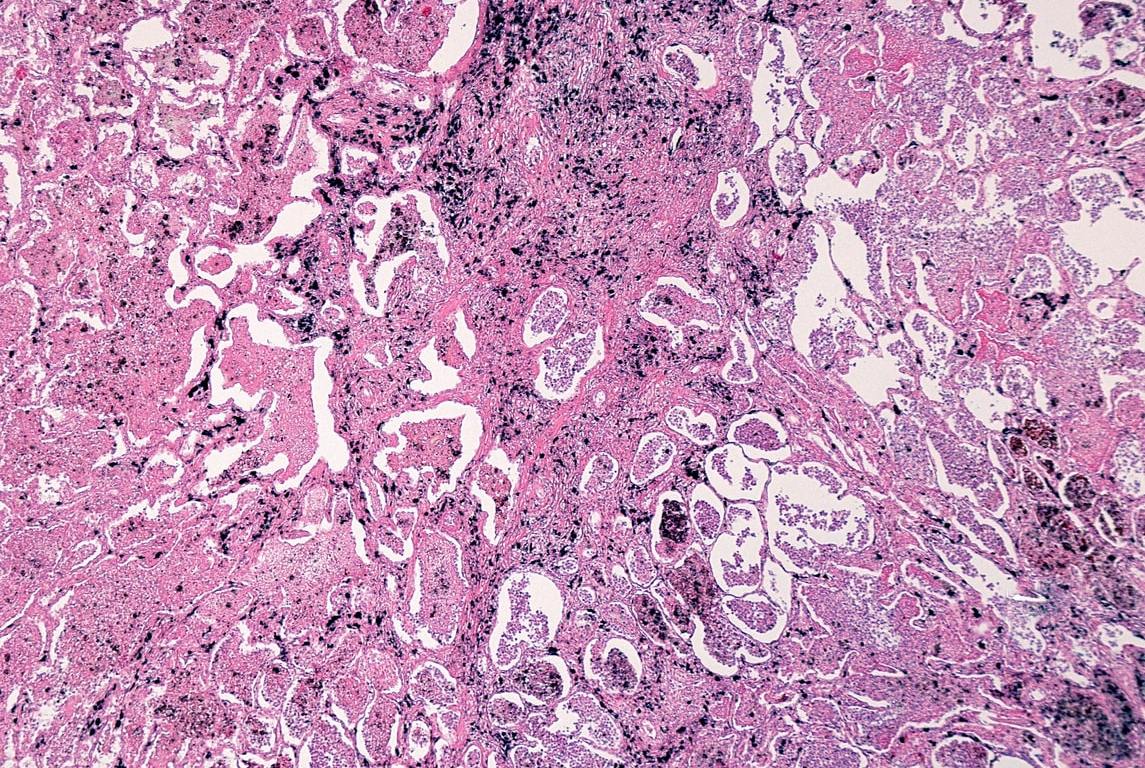

La neumoconiosis de los mineros del carbón (NMC) es la enfermedad del parénquima pulmonar producido por la inhalación y el depósito del polvo del carbón y la reacción titular que provoca, también conocida como »la enfermedad del pulmón negro», es una enfermedad ocupacional que necesita una exposición de 5-10 años.

En la radiología se destacan pequeñas opacidades menores de 1 cm, que predominan en lóbulos superiores de los pulmones y se van extendiendo al resto del pulmón.

Los trabajadores quedan »marcados» con la enfermedad y pueden llegar a formas complicadas como la fibrosis masiva progresiva, caracterizada por opacidades mayores de 1 cm que predomina de igual manera en lóbulos superiores, siendo potencialmente mortal.

Las personas que padecen artritis reumatoide y que han inhalado polvo del carbón pueden presentar el síndrome de Caplan, que consiste en la asociación de nódulos pulmonares de 5 a 50 mm generalmente bilaterales y periféricos.